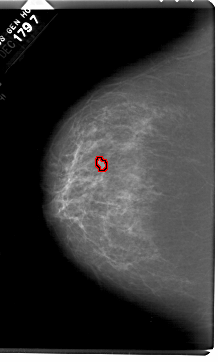

A_1518_1.LEFT_MLO

LEFT_MLO LINES 6601 PIXELS_PER_LINE 4441 BITS_PER_PIXEL 12 RESOLUTION 43.5 OVERLAY

FILE: A_1518_1.LEFT_MLO.OVERLAY

TOTAL_ABNORMALITIES 1

ABNORMALITY 1

LESION_TYPE MASS SHAPE LOBULATED MARGINS ILL_DEFINED

ASSESSMENT 4

SUBTLETY 2

PATHOLOGY BENIGN

TOTAL_OUTLINES 1

BOUNDARY